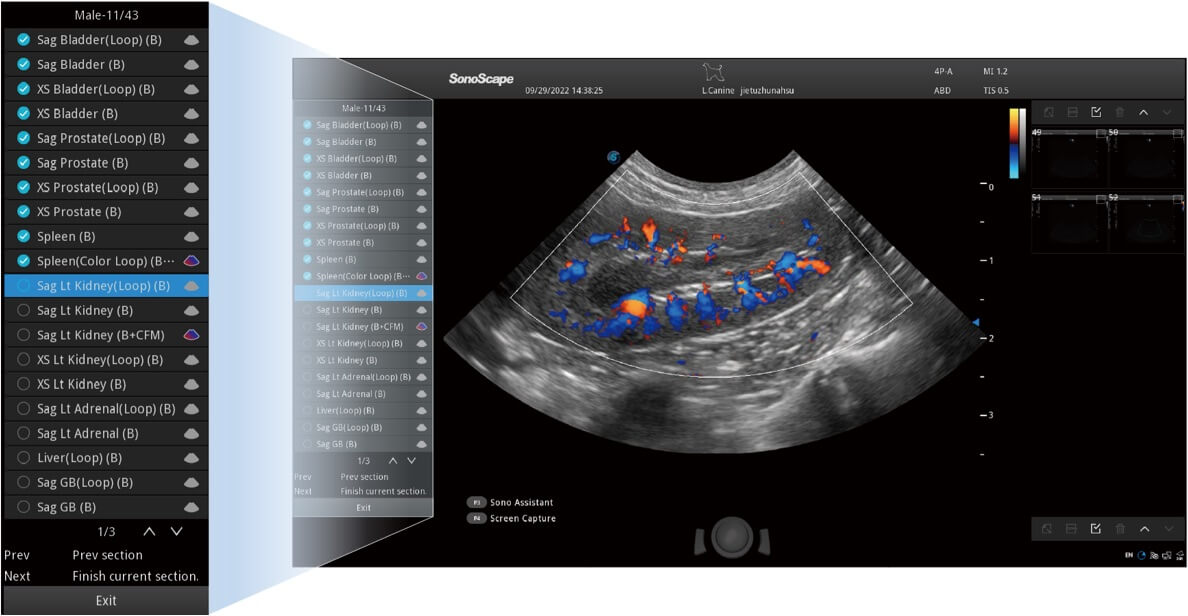

ProPet 60 作为一款高端台式动物超声设备,为动物医生的日常诊断提供了一系列贴合动物临床需求、解决临床实际问题的高级成像功能。凭借全系列高清探头,满足医生对腹部、心脏、生殖、浅表、肌骨等成像的所有需求,切实帮助您提升检查效率,提高诊断信心。